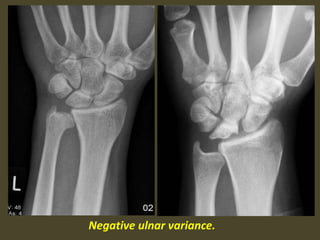

Ulnar variance may be :

Neutral (both the ulnar and radial articular surfaces at the same

level)

Positive (ulna projects more distally)

Negative (ulna projects more proximally)

negative ulnar variance is associated with Keinbock,s disease and ulnar

impingement syndrome

Negative ulnar variance secondary to TFC tear.

Negative ulnar variance.